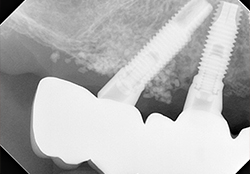

右前方インプラント頚部の骨補填材は、3年経過後も維持されている。

インプラント埋入から1年7ヶ月,X線で近心の骨吸収を認めたため,インプラント頚部のレーザー照射による除染,骨補填材の填入による骨造成を行った。粘膜を剥離すると,近心歯槽骨は吸収し,2~3スレッド露出していた。Er:YAGレーザーを50mJ 10pps 照射,表面の灰色がやや黒く変化するのを目安とした。骨補填材セラフォームを填入し,減張切開により,創の完全閉鎖を行った。

上顎インプラント埋入から3年1ヶ月,除染骨造成手術より1年6ヶ月,アバットメントレベルの印象採得を行い,ジルコニア最終上部構造連結した。

除染骨造成手術より3年経過したが、特に問題は起きていない。